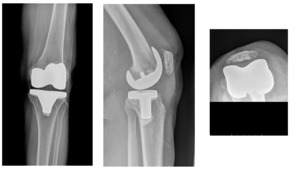

As was previous reported at the two- and five-year post-operative follow-up, between November 2010 and December 2013, the senior author performed 176 consecutive primary TKAs in 172 patients, without selection, utilizing the posterior stabilized (PS) Freedom Total Knee® system (MAXX Orthopedics, Inc., Plymouth Meeting, Pennsylvania) (FIGURE 1) (S. Durbhakula and Rego 2016; S. D. Durbhakula and Durbhakula 2019). The Freedom Total Knee system was originally introduced in 2007 and is manufactured from cast cobalt chromium (ASTM F-75 CoCrMo), and the articular bearing surfaces use ram-extruded UHMWPE (GUR 1020). When introduced, multiple “state of the art” design considerations was unique to this component design and remains highly relevant to the success of primary TKA, and unchanged to this date.

Of the 172 patients originally studied, there were 129 females (75.0%) and 43 males (25.0%) with an average patient age at surgery of 69.7 ±7.6 years (range: 52.3 years to 98.6 years). The average age of the female patient (69.3 years) when compared to the male patients (70.7 years) was not significantly different (p=0.311) (Table 1). In this continuous series, four female patients underwent bilateral TKA under the same anesthesia. In this set of patients, the pre-operative diagnosis was predominantly degenerative joint disease (DJD) in 170 knees (96.6%) and rheumatoid arthritis (RA) in 6 knees (3.4%). The surgical side was evenly distributed across all patients with 86 left (48.9%) and 90 right (51.1%) knees (Table 1). In all cases a tourniquet was used and a standard deep-vein thrombosis (DVT) prophylaxis of Lovenox® implemented (Sanofi-Aventis, Bridgewater, NJ). Additionally, summary of the previously 2- and 5-year reported data is listed in TABLES 1 and 2.